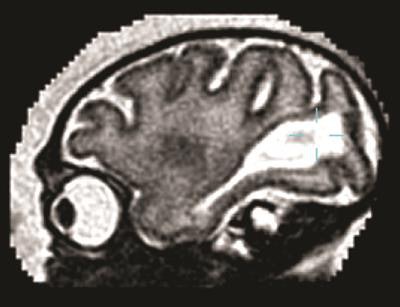

The first MRI scan of the fetal brain was performed 10 days after inoculation and showed hyperintense foci in the occipital-parietal regions surrounding the lateral ventricles. Eventually, the hyperintense foci enlarged on the right side but reversed and became hypointense on the left, which was linked with a loss of brain volume and ventricular collapse.

"We were shocked when we saw the first MRI of the fetal brain 10 days after viral inoculation. We had not predicted that such a large area of the fetal brain would be damaged so quickly," added co-author Dr. Lakshmi Rajagopal, an associate professor of pediatrics, in the statement.

The researchers also tracked another fetal brain anomaly. Large posterior ventricular cerebrospinal fluid spaces remained late into the unborn primate's gestation, along with increased water content in surrounding posterior white matter. Under normal conditions, those regions become smaller as the parietal and occipital lobes develop late in the pregnancy.

The MR images revealed no abnormalities in the cortical area, brainstem, or cerebellum. There also were no indications of injury in other maternal or fetal organs. The Zika viral genome, however, was present in other fetal tissues, including the eye, liver, and kidney.